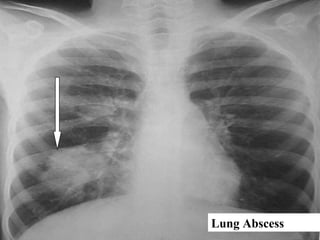

Lung Abscess

 Lung Abscess is localized area of suppurative necrosis within

the pulmonary parenchyma, resulting in the formation of one

or more large cavities.

 Variable size , may be single or multiple , depending on mode

of development.

 Aspiration - Usually solitary , more in RL

 Postpneumonic - usually multiple, more basal

 Hematogenous - usually multiple at any site

 Culture of pus - often mixed aerobic / anaerobic

 Histology - focus of suppuration (neutrophils) surrounded by

fibrous scarring and mixed chronic inflammatory cells

 Healing by fibrosis leaving a sterile cavity

Complications of lung abscess

*Radiological picture → Air- Fluid level

*Rupture into pleura → Empyema

*Rupture into bronchus →Bronchopneumonia

 Formation bronchopleural fistula → Pneumothorax

 Septic emboli

 Lung hemorrhage from vessels in fibrous wall